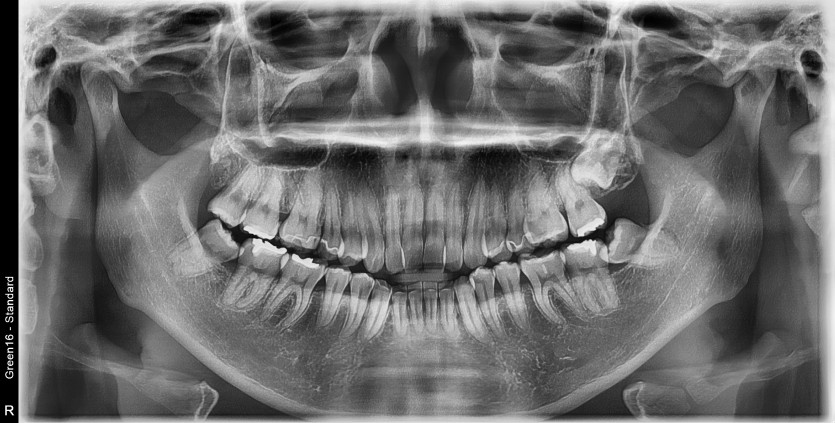

#18,48 사랑니 발치

구강 외과 전문의가 당일 발치했습니다.